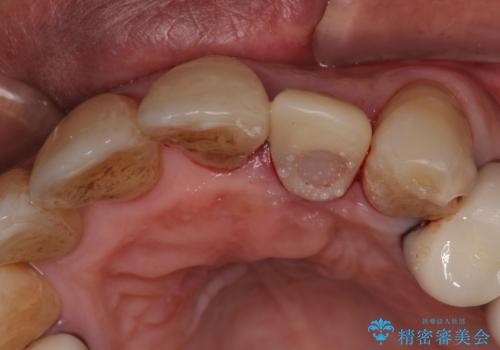

- 前歯のセラミッククランが外れてしまったとのことで来院された患者様です。

診察をしたところ、歯根に縦破折が認められ、抜歯が必要と判断されました。

抜歯、インプラント埋入、仮歯の装着が同時に可能な1DAYインプラントが適用可能と判断されたため、インプラントによる補綴治療を行うこととしました。